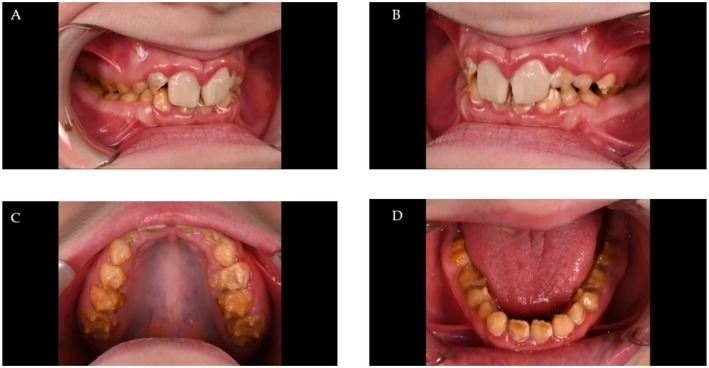

Results: The clinical phenotype of the affected individuals showed a generalized and extensive enamel defect of all teeth. In the exome dataset of the proband, a novel nonsense variant in FAM83H, c.1055C>A p.(Ser352*) was detected, which was verified by conventional Sanger sequencing. Co-segregation analysis confirmed that the variant was present in all affected individuals and not in unaffected individuals.